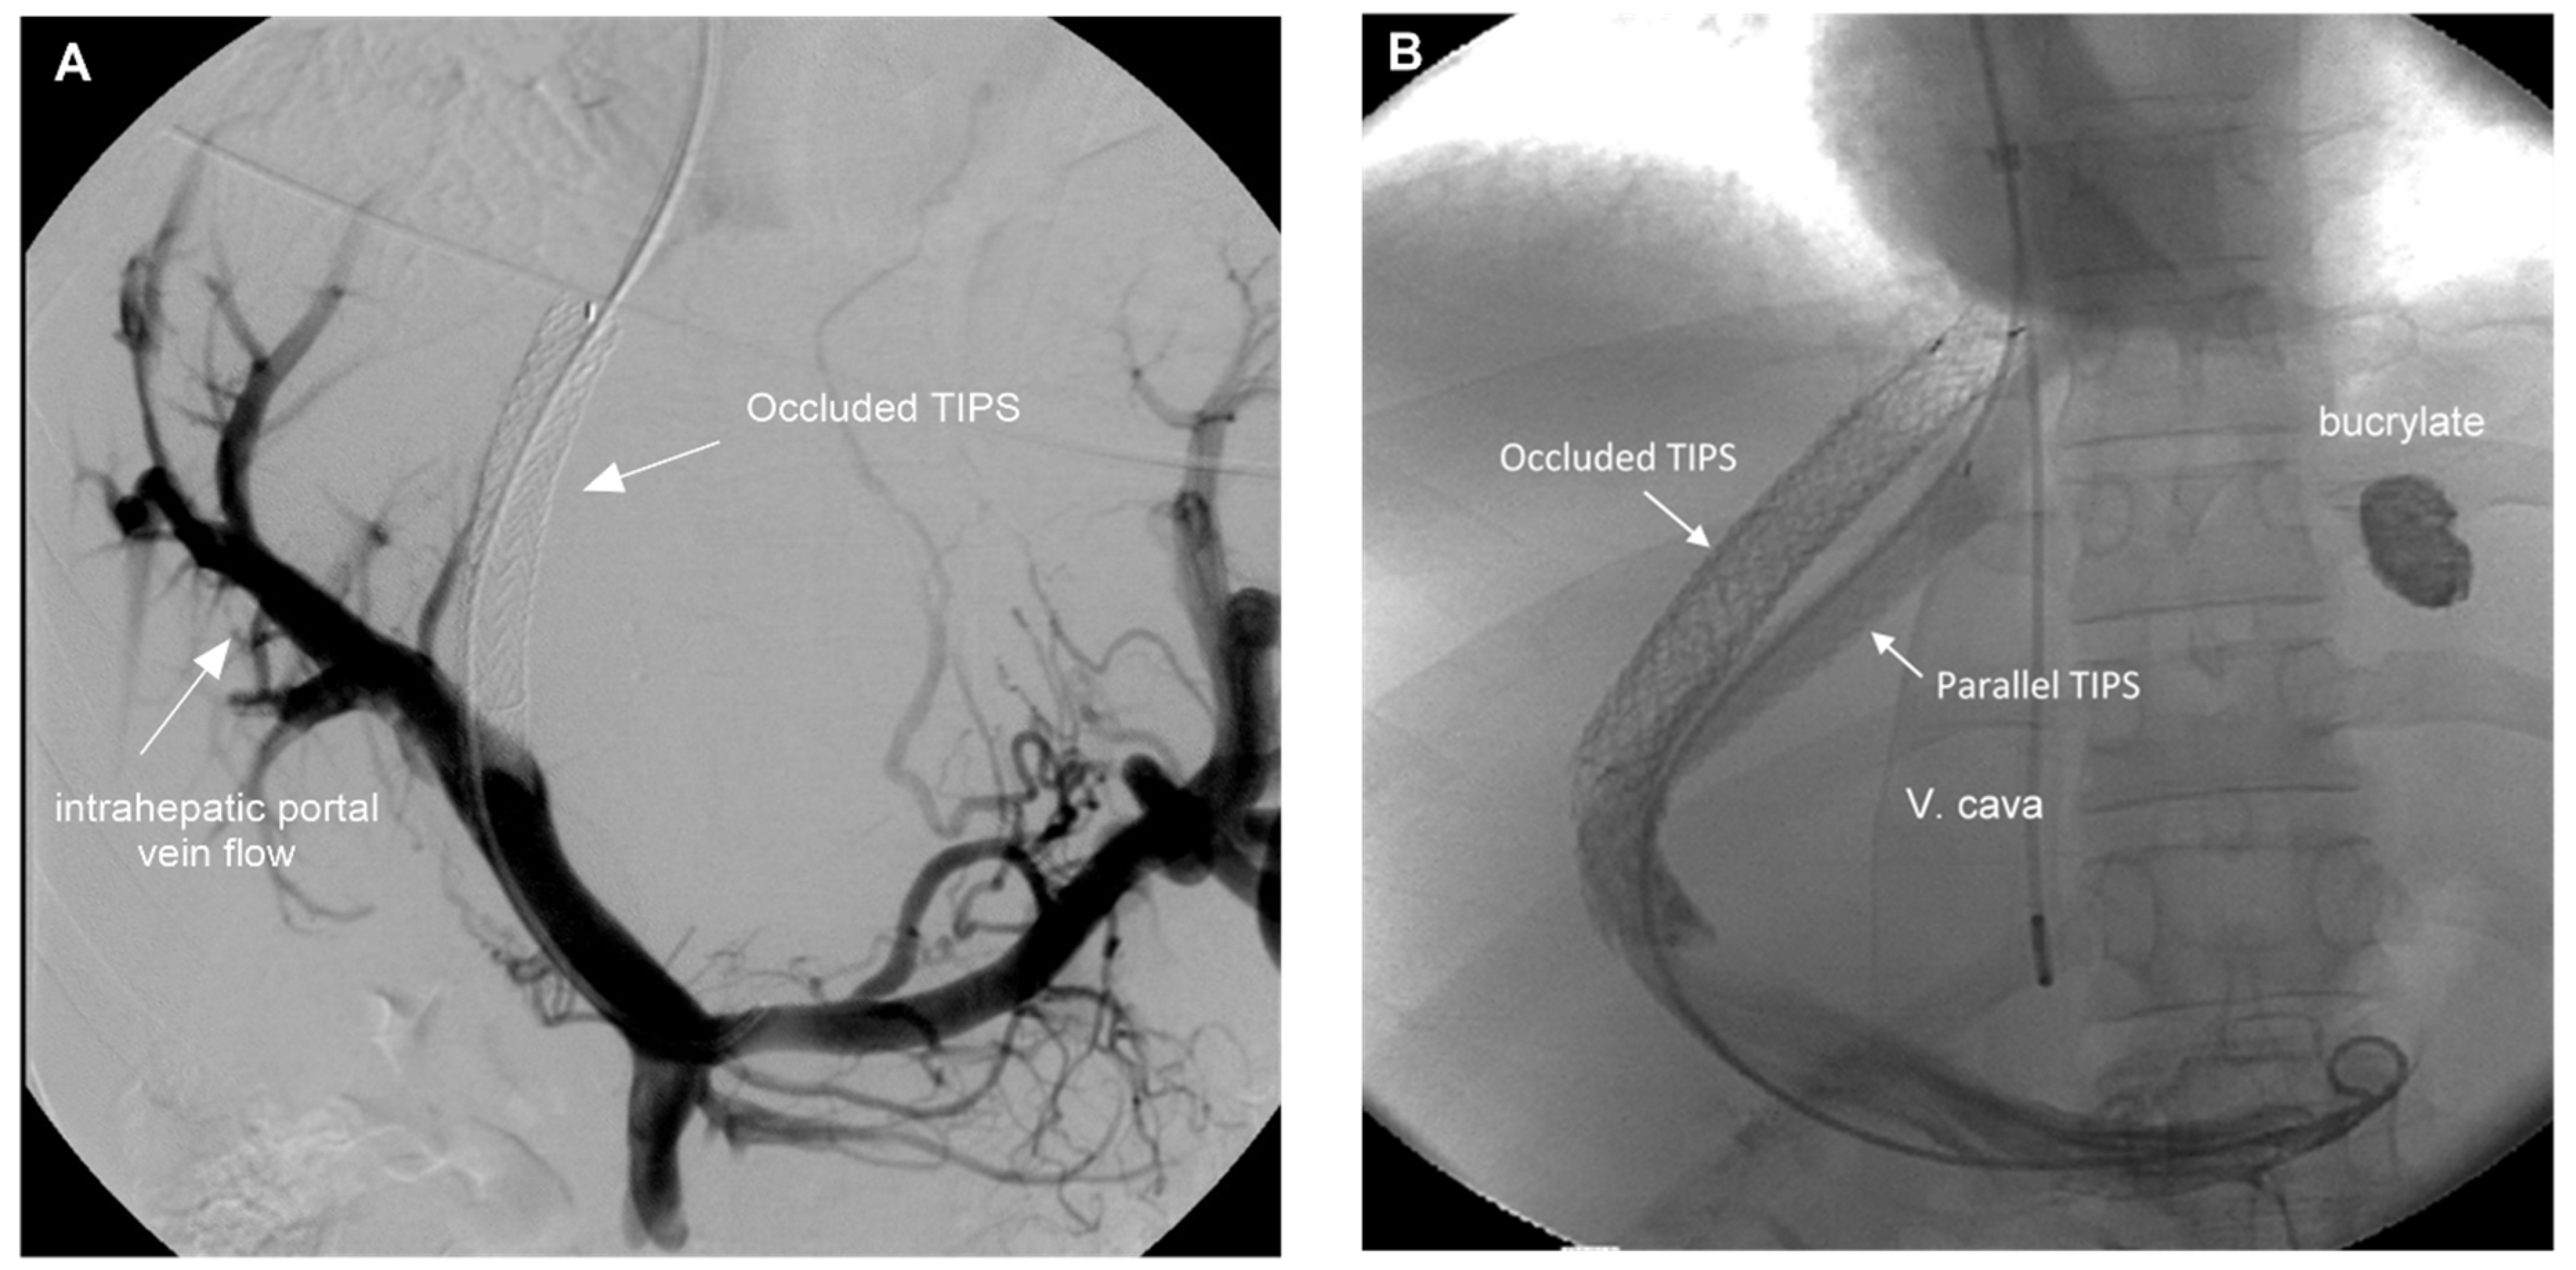

3.3. Shunt Patency